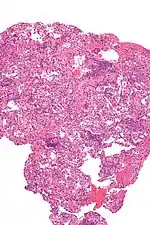

Micrograph showing lung transplant rejection. Lung biopsy. H&E stain.

As with any surgical procedure, there are risks of bleeding and infection. The newly transplanted lung itself may fail to properly heal and function. Because a large portion of the patient's body has been exposed to the outside air, sepsis is a possibility, so antibiotics will be given to try to prevent that. Other complications include Post-transplant lymphoproliferative disorder, a form of lymphoma due to the immune suppressants, and gastrointestinal inflammation and ulceration of the stomach and esophagus.

Transplant rejection is a primary concern, both immediately after the surgery and continuing throughout the patient's life. Because the transplanted lung or lungs come from another person, the recipient's immune system will see it as an invader and attempt to neutralize it. Transplant rejection is a serious condition and must be treated as soon as possible.